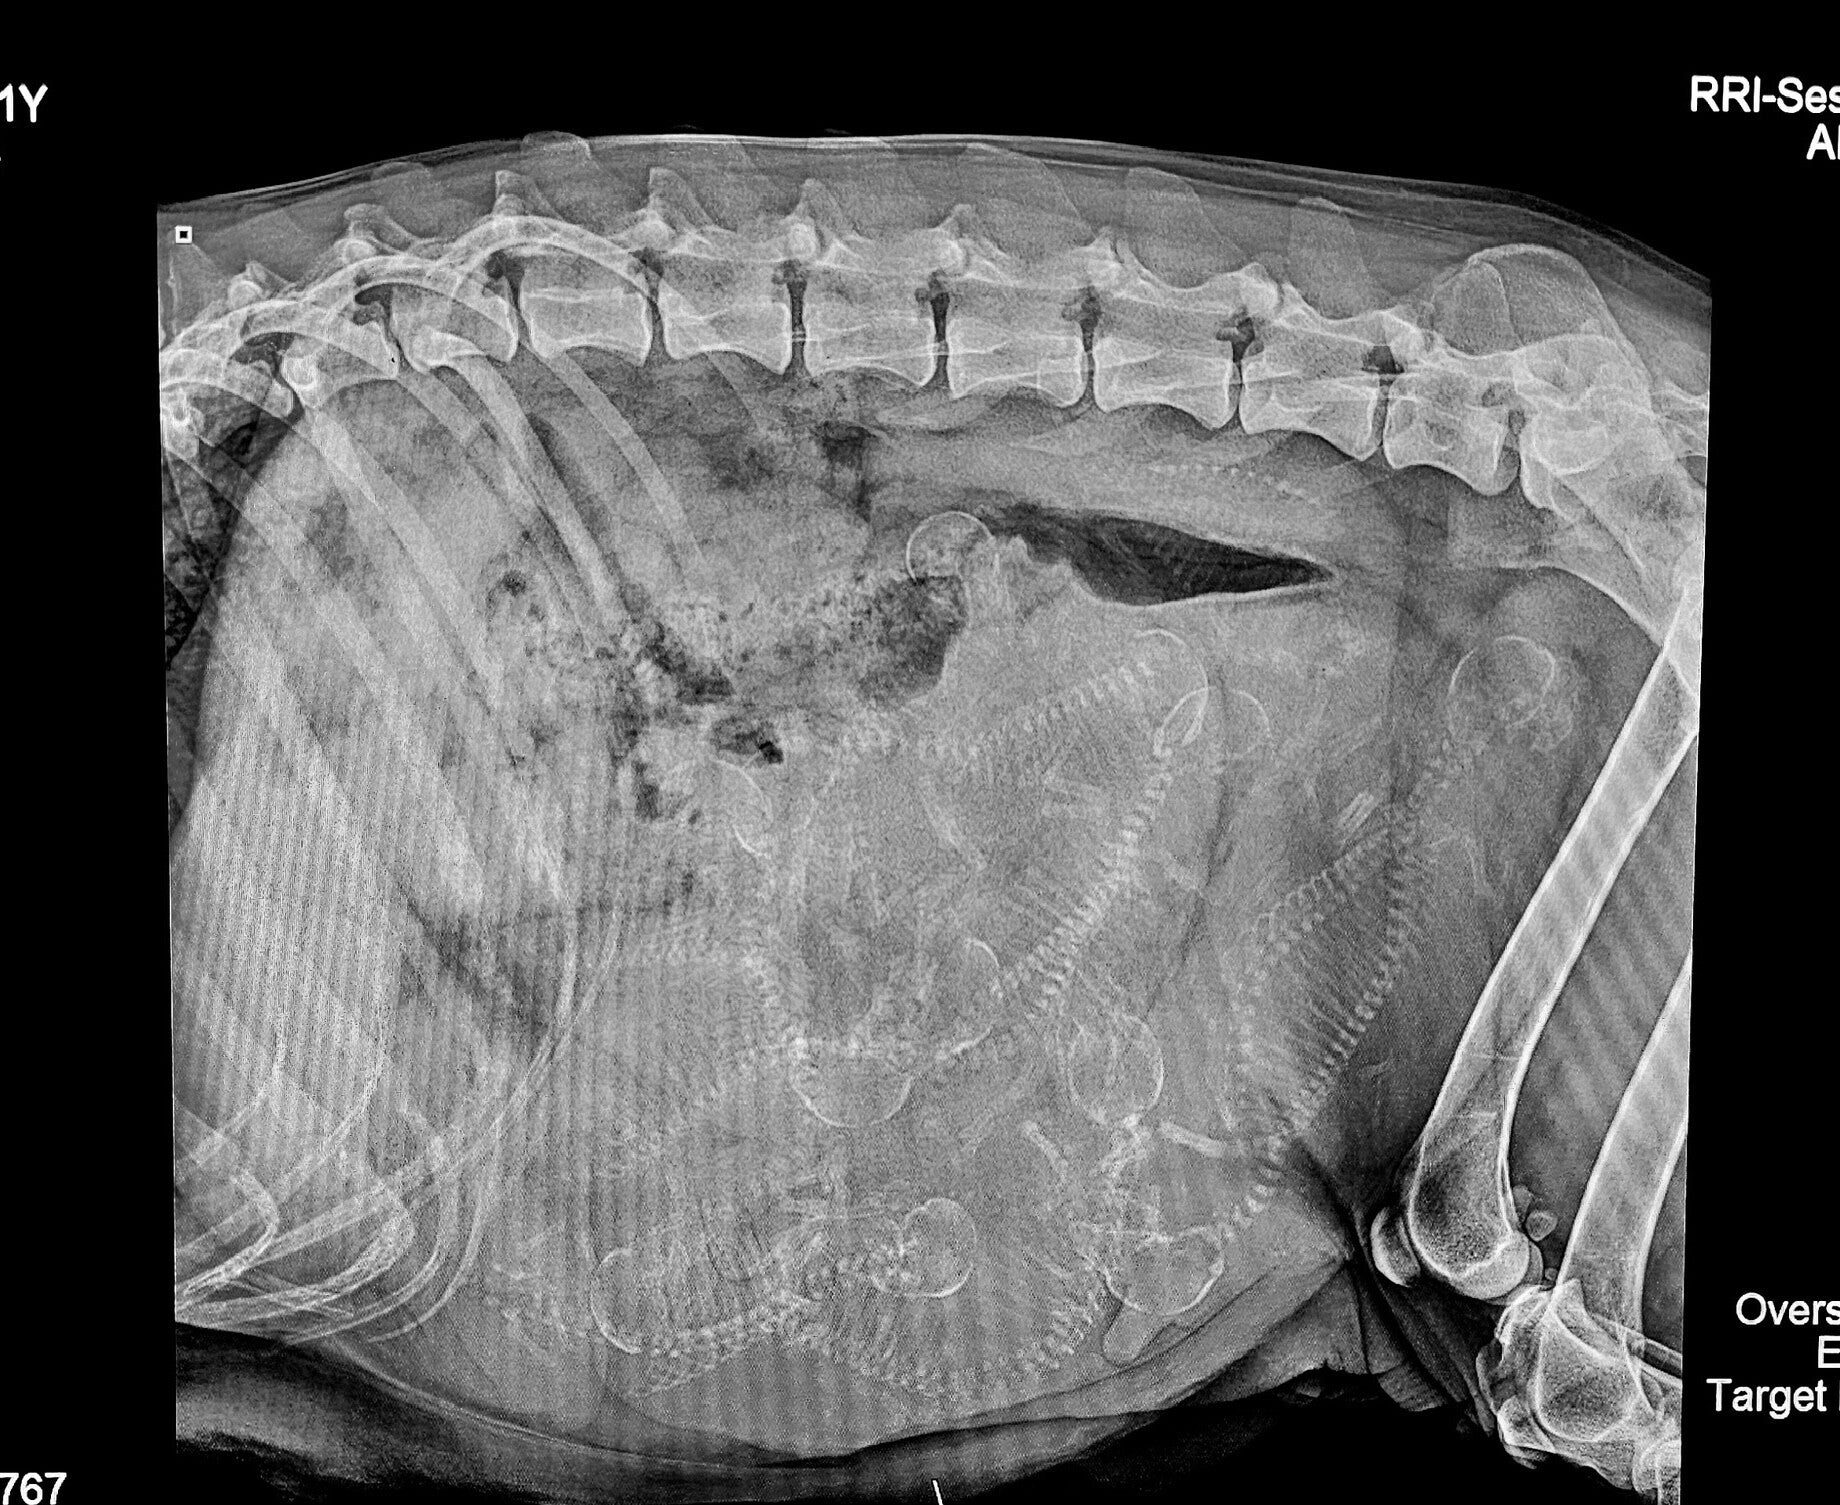

Gabbi's 53 Day Prenatal X-ray

Gabbi had her puppy count X-ray today. 5-7 developing puppies is now more like 12! It's going to be a big litter. We have her due date at Feb 21st, but I'll be surprised if she doesn't go early. We are so excited to welcome a dozen little ones to the world!

Original picture